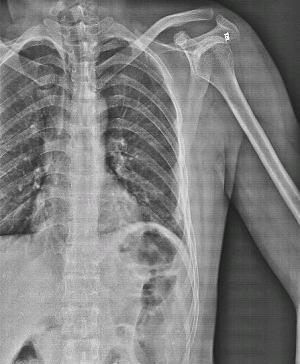

肋骨骨折一般有横型骨折,斜型骨折,螺旋型骨折,三小时后患者呼吸困难,用手捂住骨折处才能敢慢慢呼吸,呼吸有骨擦音,大小便都会疼痛,走路不能直腰,向患侧倾斜身体。